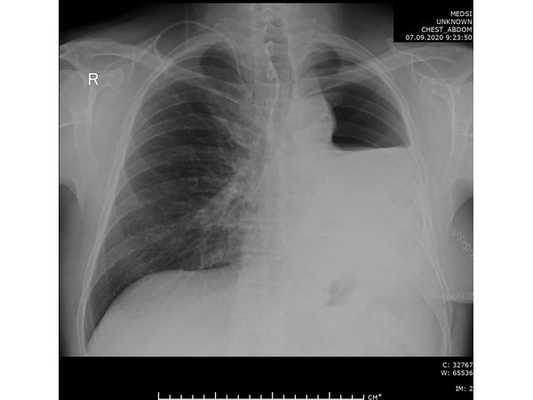

Несмотря на это, первые признаки онкологии легких у женщин во многом зависит от локализации опухоли и ее гистологическому виду. При периферическом расположении рака прогноз оптимистичный. Сам процесс онкообразования протекает медленно, растягиваясь на годы. Пациентка не догадывается о наличие рака легких, пока случайно не обнаружится округлое затемнение на рентгенограмме. С другой стороны, при центральном расположении - все основные признаки рака легких у женщин появляются очень быстро и рано. Наиболее утешительный прогноз при таком течение - 3-4 года.

Врачи онкологического центра Юсуповской больницы настоятельно рекомендуют прохождение плановой рентгенодиагностики хотя бы раз в год для всех женщин. Получив грамотную консультацию от ведущих специалистов страны в области онкологии, пациенту составляется индивидуальный план лечения. В клиники онкологии Юсуповской больницы используется комплексный подход в тактике ведения больного, его консультируют множество смежных специалистов для разработки программы реабилитации после хирургического лечения либо химиотерапии.

К сожалению, заболевание на ранней стадии выявляется редко, поскольку оно не имеет выраженной клинической картины. Происходит незначительное ухудшение состояния, которое больной может воспринимать как обычное недомогание. В большинстве случаев рак легких 1 стадии выявляют случайно во время профилактических осмотров или при исследовании другой патологии.

- рентгенографию легких в 2-х проекциях, линейную томографию, КТ легких;

- Лучевая диагностика. В обязательном порядке всем больным проводится двухпроекционная рентгенография легких. Рентгенпризнаки центрального рака легкого представлены наличием шаровидного узла в корне легкого и расширением его тени, ателектазом, обтурационной эмфиземой, усилением легочного рисунка в зоне корня. Линейная томография корня легкого помогает уточнить размер и локализацию опухоли. КТ легких информативно для оценки взаимоотношения опухоли с сосудами легких и структурами средостения.